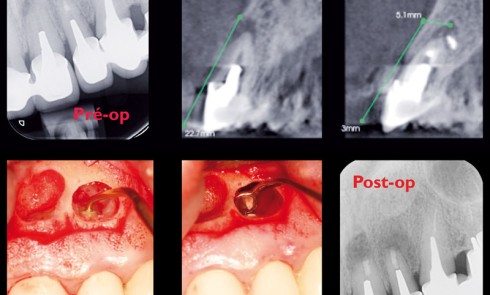

Article réservé à nos abonnés Imagerie en implantologie orale : étude pré-implantaire et planification

L’imagerie en implantologie orale est un élément essentiel de la démarche diagnostique, de la sélection des patients et de la...